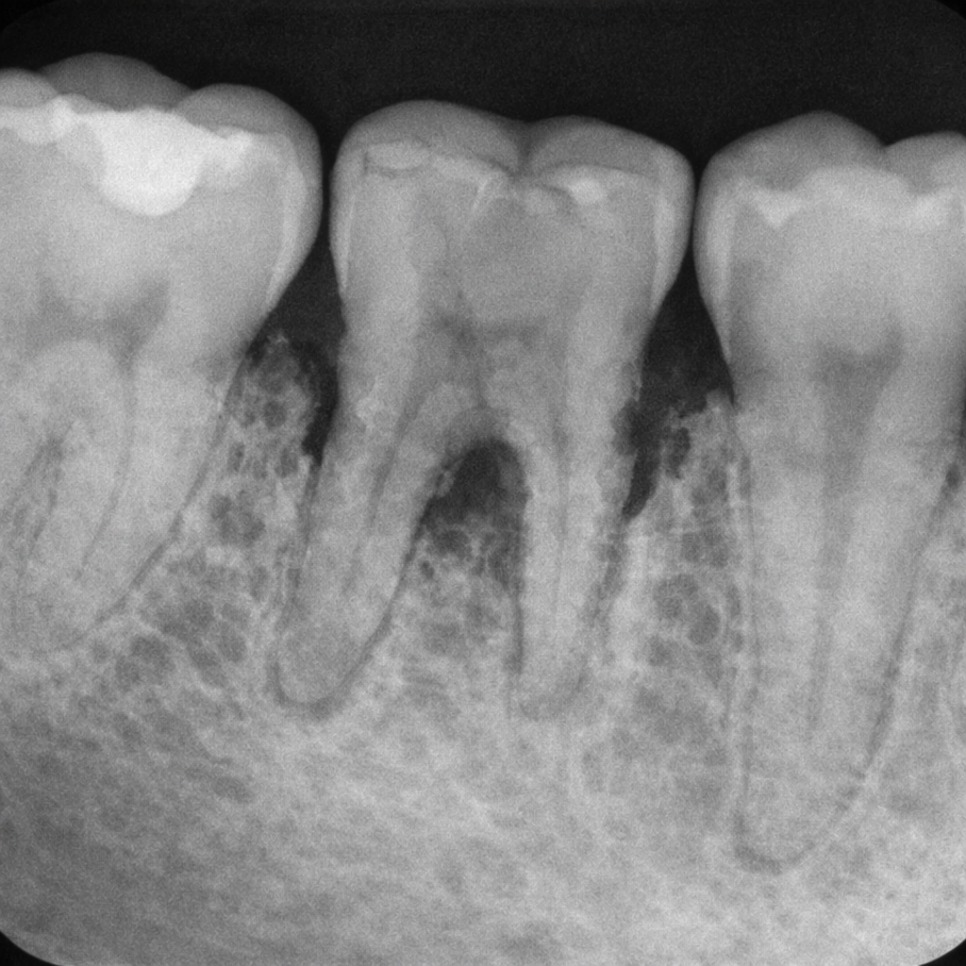

치주염은 치은염이

충분히 관리되지 않아

염증이 치조골과 치주인대까지

파고든 상태를 말합니다.

세균이 만들어내는 독소와

우리 몸의 면역 반응이 맞물리면서

치아를 받치는 뼈가 조금씩 파괴됩니다.

한번 소실된 치조골은

자연적으로 회복되지 않기 때문에,

치은염과 달리 비가역적(irreversible)인

변화를 남긴다는 점이 핵심입니다.

증상으로는 잇몸 퇴축에 따른

뿌리 노출, 치아 사이 공간 증가,

씹을 때의 불편감이 나타나며,

심한 경우에는

치아 흔들림으로

이어지기도 합니다.

치은염과 치주염을

구분하는 핵심 검사는

치주낭 깊이 측정(probing)입니다.

가느다란 탐침을

잇몸과 치아 사이 틈새에 넣어

깊이를 수치로 확인하는 방식으로,

정상 범위는 1~3mm 이내입니다.

4mm 이상부터는 치주 조직에

병적인 변화가 생긴 것으로 보며,

5~6mm 이상이면 적극적인

처치가 필요한 치주염으로 판단합니다.